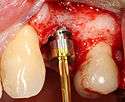

- Soft tissue reflection: An incision is made over the crest of bone, splitting the thicker attached gingiva roughly in half so that the final implant will have a thick band of tissue around it. The edges of tissue, each referred to as a flap are pushed back to expose the bone. Flapless surgery is an alternate technique, where a small punch of tissue (the diameter of the implant) is removed for implant placement rather than raising flaps.

- Drilling at high speed: After reflecting the soft tissue, and using a surgical guide or stent as necessary, pilot holes are placed with precision drills at highly regulated speed to prevent burning or pressure necrosis of the bone.

- Drilling at low speed: The pilot hole is expanded by using progressively wider drills (typically between three and seven successive drilling steps, depending on implant width and length). Care is taken not to damage the osteoblast or bone cells by overheating. A cooling saline or water spray keeps the temperature low.

- Placement of the implant: The implant screw is placed and can be self-tapping,[18](pp100–102) otherwise the prepared site is tapped with an implant analog. It is then screwed into place with a torque controlled wrench[19] at a precise torque so as not to overload the surrounding bone (overloaded bone can die, a condition called osteonecrosis, which may lead to failure of the implant to fully integrate or bond with the jawbone).

- Tissue adaptation: The gingiva is adapted around the entire implant to provide a thick band of healthy tissue around the healing abutment. In contrast, an implant can be "buried", where the top of the implant is sealed with a cover screw and the tissue is closed to completely cover it. A second procedure would then be required to uncover the implant at a later date.